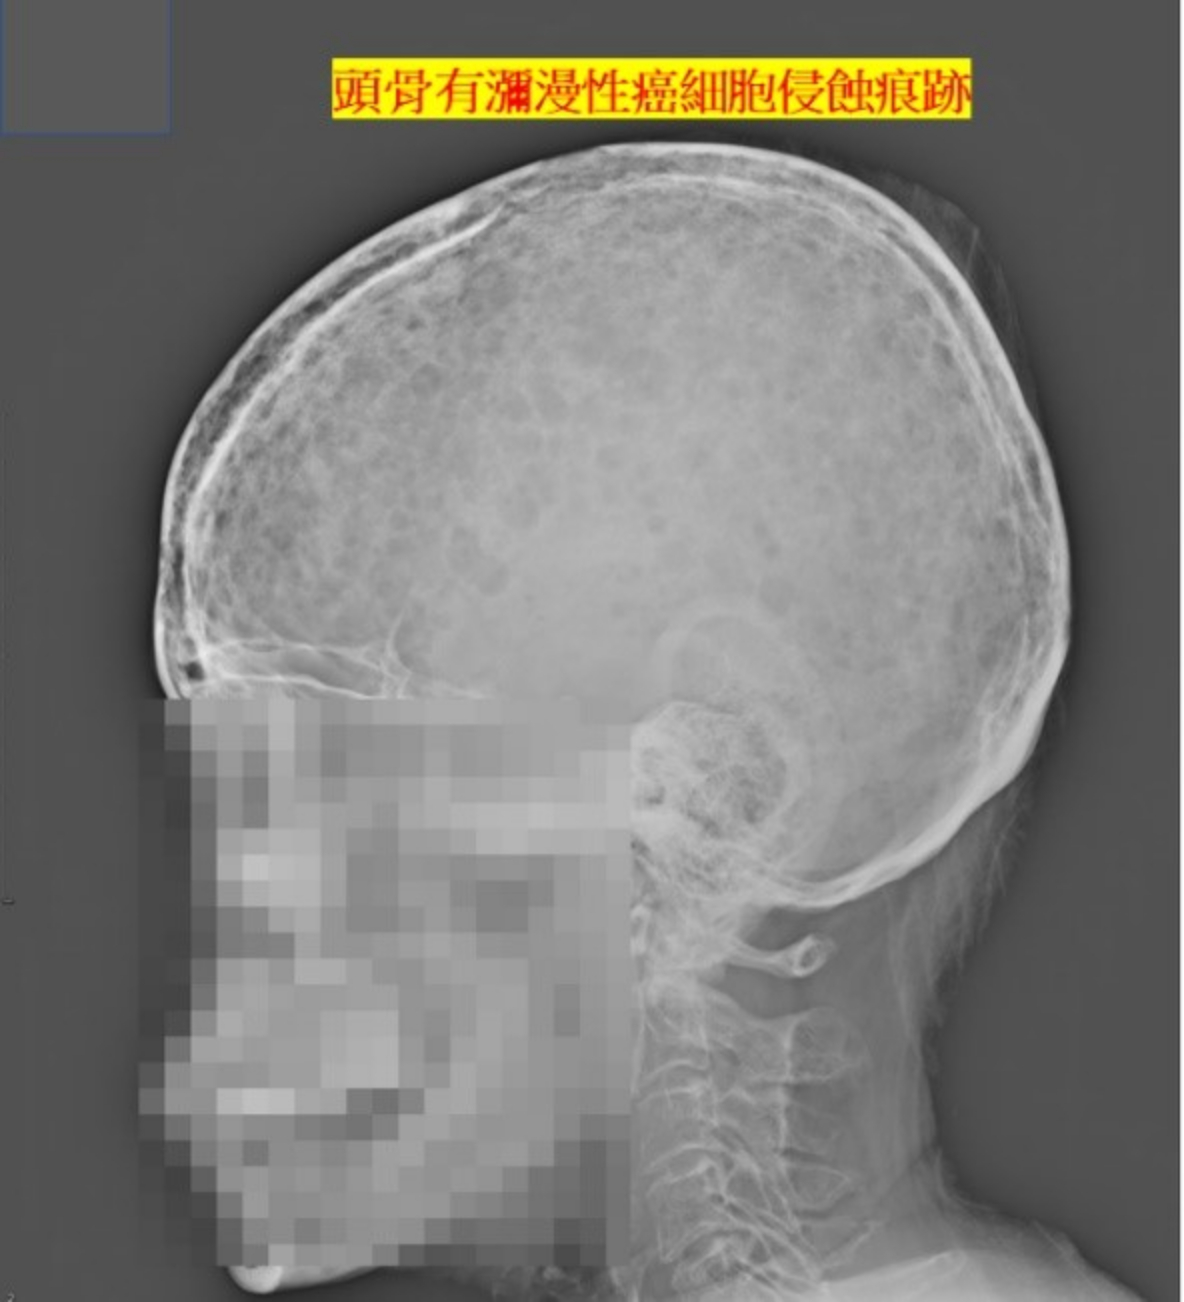

另一名50餘歲女性,因右側腎結石及全身瀰漫性疼痛來本院泌尿科就診,經抽血檢查發現她還同時有貧血、腎功能不全、及高血鈣症。患者原先以為是腎結石造成全身上下的不適症狀,然而在我們經驗上,單就右腎2公分的結石,無法解釋她的全身的病症,顯然除了腎結石,還有其他的問題。

我們綜合她的臨床數據,經由縝密的思考及推理,逐漸找出她的病因,最後在血液腫瘤團隊進行骨髓切片,證實多發性骨髓瘤(multiple myeloma)的診斷。多發性骨髓瘤,是一種位於骨髓內漿細胞轉化為癌細胞並大量增生的疾病,在疾病演進的過程,會造成貧血、腎功能不全、高血鈣症、及全身性骨痛等病症。

醫學文獻中提到多發性骨髓瘤與泌尿道結石的案例不多,一般認為與高血鈣症或癌細胞分泌過多的蛋白沉積於泌尿道有關。該患者的結石經由軟式輸尿管鏡成功的清除,多發性骨髓瘤的部份由本院血液腫瘤科持續治療。